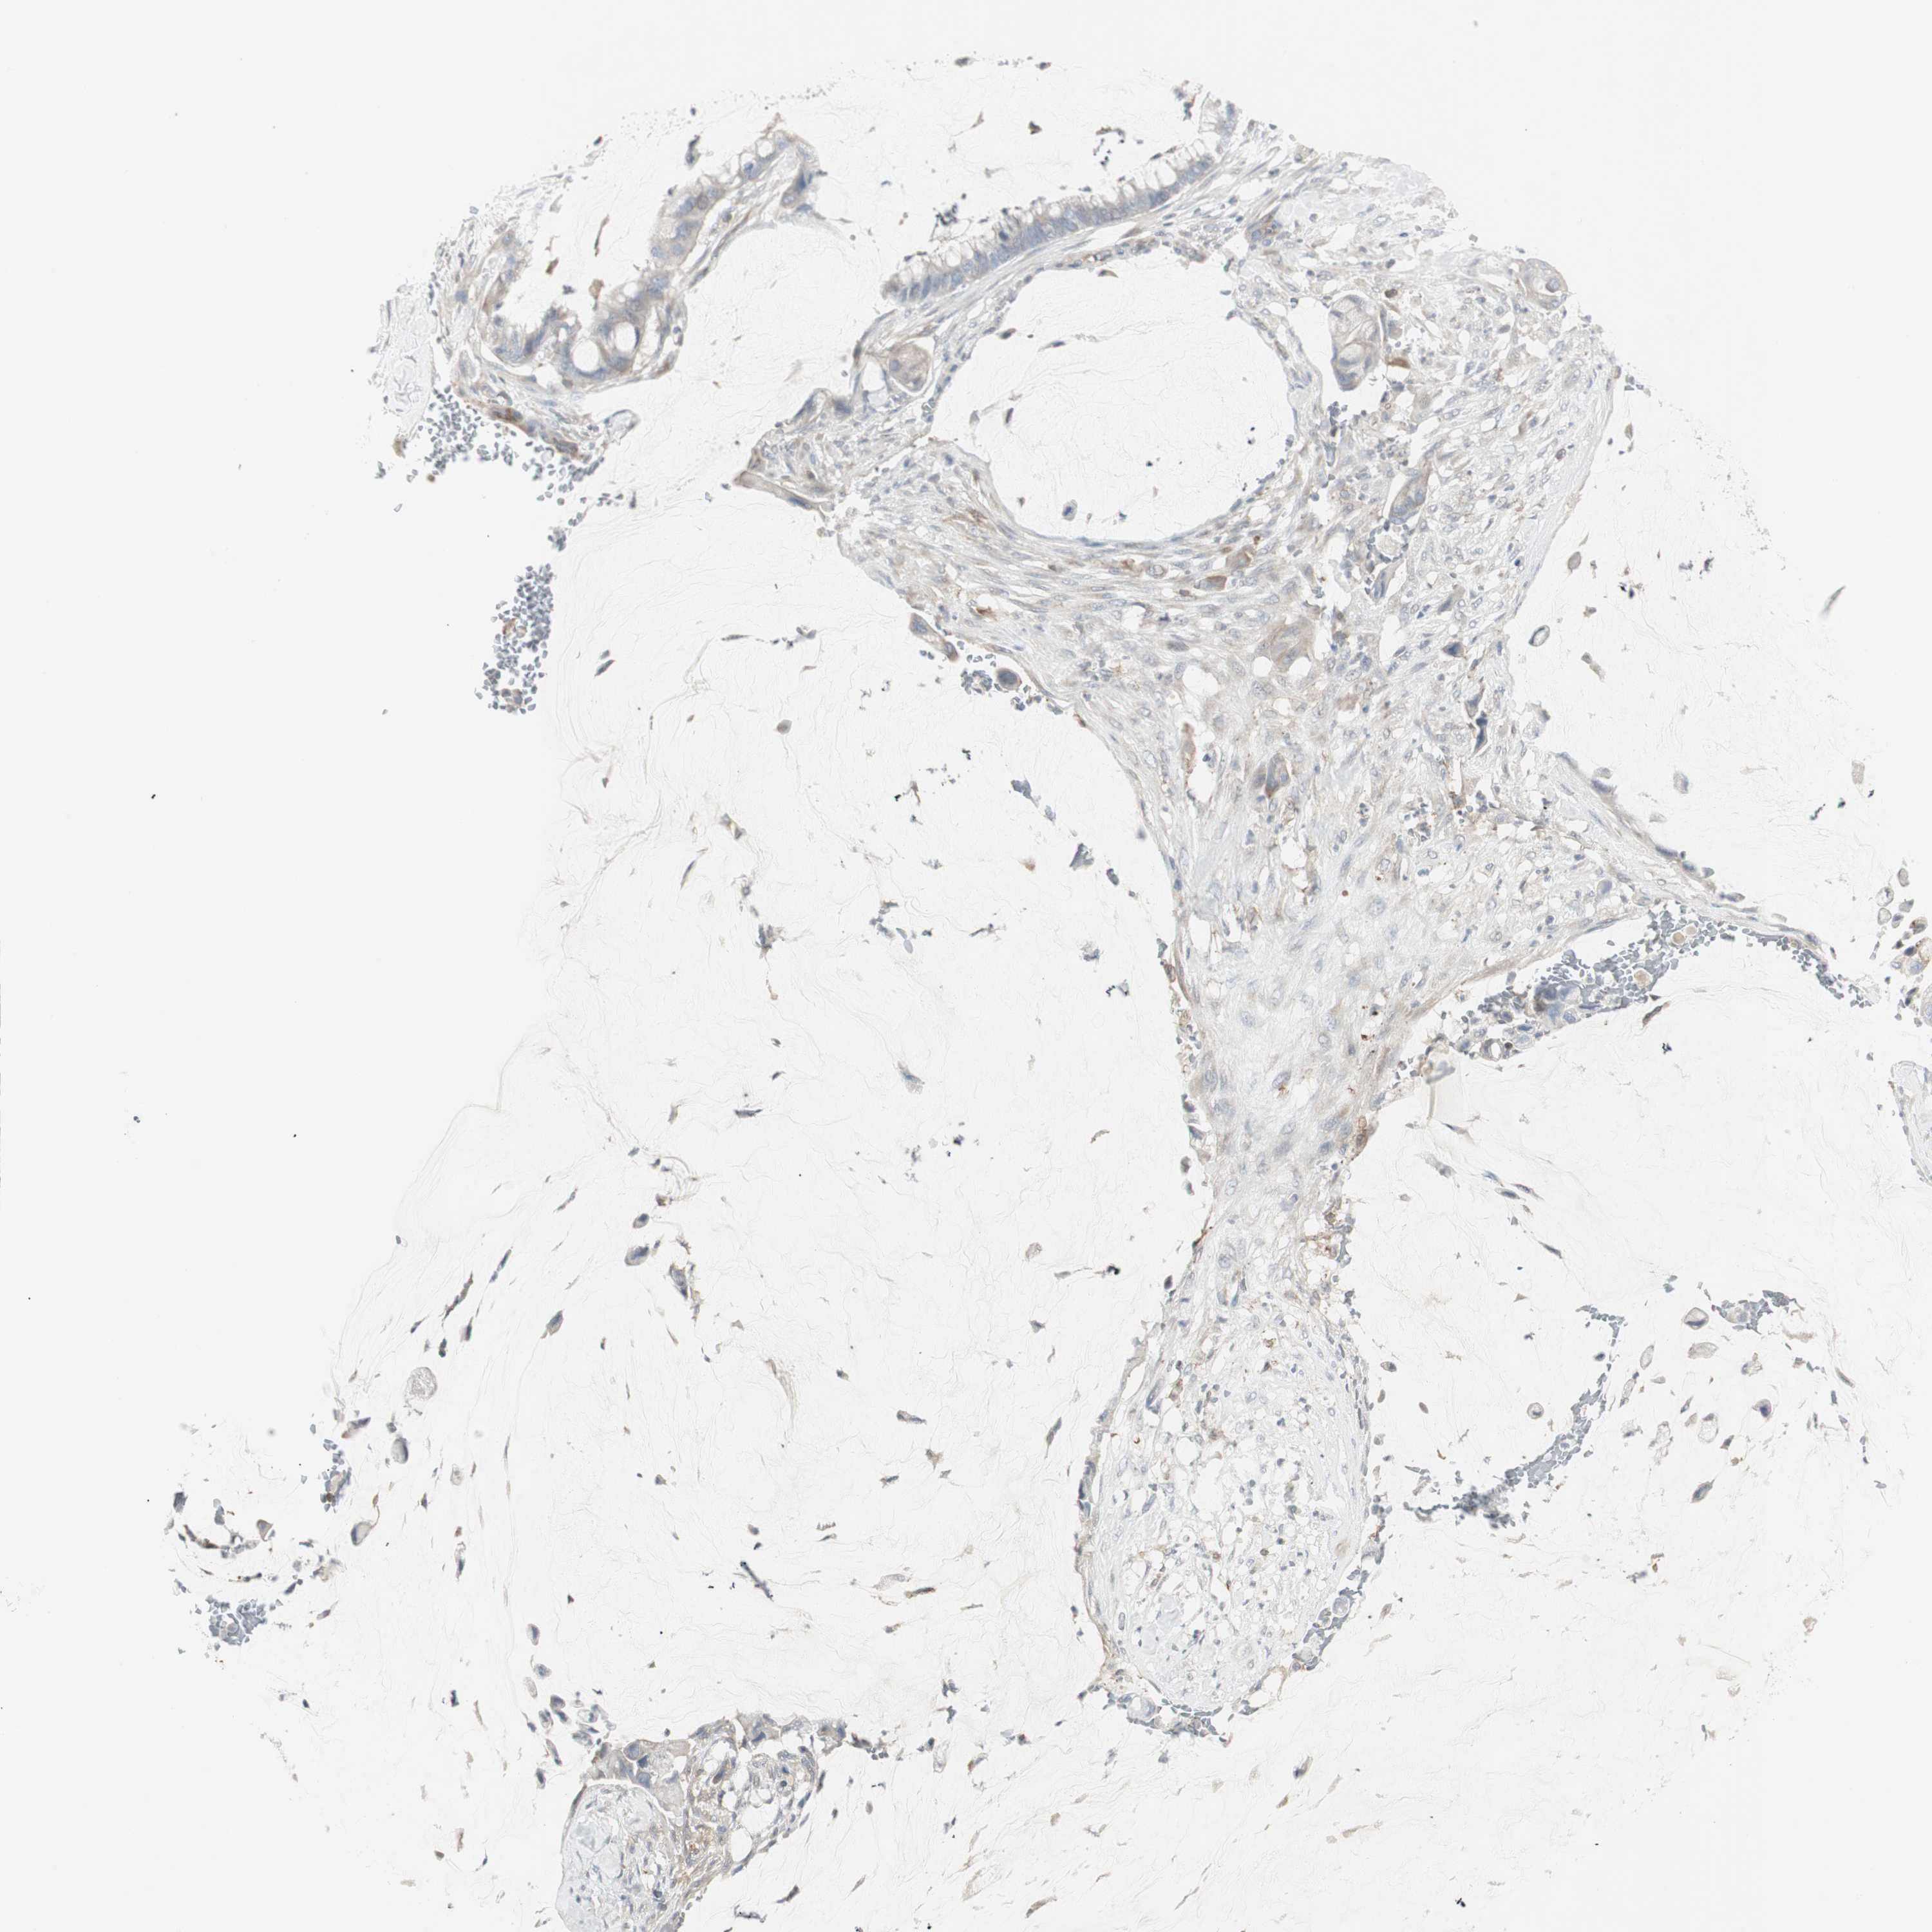

PANCREATIC CANCER - Protein expressioni

A mouse-over function shows sample information and annotation data. Click on an image to view it in a full screen mode. Samples can be filtered based on level of antibody staining by selecting one or several of the following categories: high, medium, low and not detected. The assay and annotation is described here.

Note that samples used for immunohistochemistry by the Human Protein Atlas do not correspond to samples in the TCGA dataset.

Antibody stainingi

Antibody staining in the annotated cell types in the current human tissue is reported as not detected, low, medium, or high, based on conventional immunohistochemistry profiling in selected tissues. This score is based on the combination of the staining intensity and fraction of stained cells.

Each image is clickable and will lead to virtual microscopy that enables deeper exploration of all samples and also displays staining intensity scores, fraction scores and subcellular localization as well as patient and tissue information for each sample.

Antibody HPA008476

Staining

High

Medium

Low

Not detected

Intensity

Strong

Moderate

Weak

Negative

Quantity

>75%

75%-25%

<25%

None

Location

Nuclear

Cytoplasmic/membranous

Cytoplasmic/membranous,nuclear

Adenocarcinoma, NOS